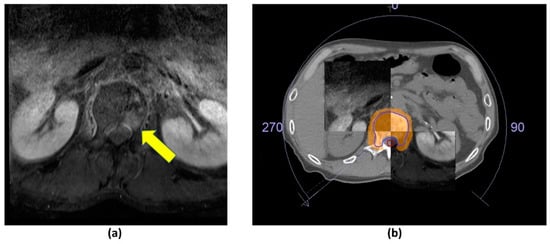

4. The Role of Imaging in Stereotactic Body Radiotherapy (SBRT)

4.1. Pre-Treatment Planning